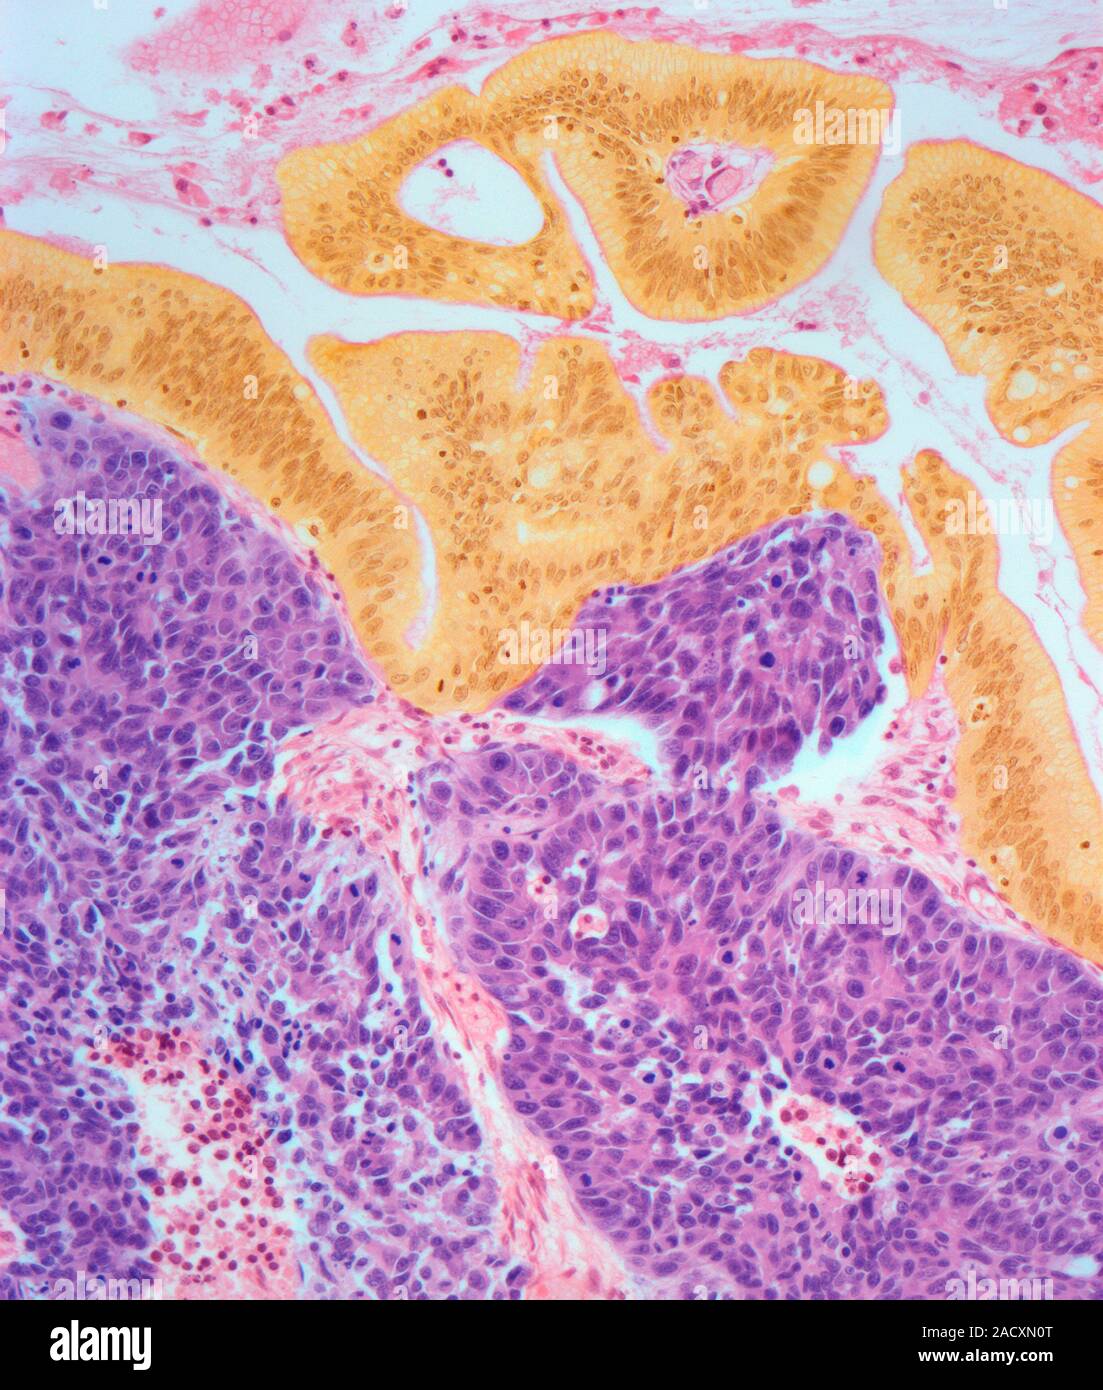

From www.alamy.com

Cervical cancer. Light micrograph (LM) of a section of a large cell Neuroendocrine Cancer Cervix Neuroendocrine carcinoma of the cervix (necc) is a rare variant of cervical cancer. Neuroendocrine carcinoma of the cervix (necc) is a rare variant of cervical. This study aims to investigate the. Aims neuroendocrine carcinoma of the cervix (necc) is a rare variant of cervical cancer. Cervical small cell neuroendocrine carcinoma (scnec) is a rare invasive cancer, accounting for no more. Neuroendocrine Cancer Cervix.

Cervical cancer. Light micrograph (LM) of a section of a large cell Neuroendocrine Cancer Cervix Neuroendocrine carcinoma of the cervix (necc) is a rare variant of cervical cancer. Neuroendocrine carcinoma of the cervix (necc) is a rare variant of cervical. This study aims to investigate the. This topic review will cover the epidemiology, clinical presentation, staging, and treatment of small cell neuroendocrine. 2 3 the 2014 world health organization (who) clas. This study aims to. Neuroendocrine Cancer Cervix.

Cervical cancer. Light micrograph (LM) of a section of a large cell Neuroendocrine Cancer Cervix Neuroendocrine carcinoma of the cervix (necc) is a rare variant of cervical. Aims neuroendocrine carcinoma of the cervix (necc) is a rare variant of cervical cancer. This topic review will cover the epidemiology, clinical presentation, staging, and treatment of small cell neuroendocrine. This study aims to investigate the clinicopathological features. 2 3 the 2014 world health organization (who) clas. Neuroendocrine. Neuroendocrine Cancer Cervix.